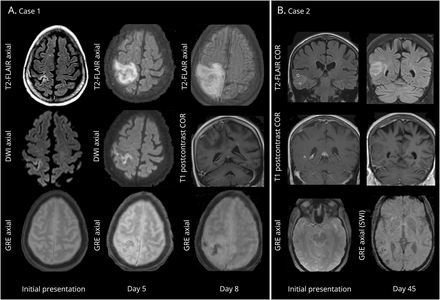

(一)案例1:上面一行:发展高T2 / fluid-attenuated反转恢复(天赋)信号/右额-顶叶水肿;中间行:温和对frontoparietal皮质基于扩散限制,微弱的正确frontoparietal旋转的增强;底下一行:进步的易感性工件(出血)梯度地区的成像信号异常。(B)案例2:上面一行:进步的高T2 /天赋信号/水肿右颞顶叶;中间行:非常微弱leptomeningeal增强区域水肿;底下一行:基于渐进皮质易感性工件(出血)地区的水肿。

MRI大脑被命令进行进一步的评估和演示了一个t2加权hyperintense质量涉及的右颞顶皮层病变局部肿胀、微妙的leptomeningeal增强,和没有限制扩散diffusion-weighted成像(图1 b)。最初的担忧包括麦麸转移和低级的神经胶质瘤。脑活检是推荐,显示nongranulomatous坏死性血管炎与小血管leptomeningeal破坏性变化(图e 1中,links.lww.com/WNL/A381)。

影像学发现典型的转移。基于成像显示皮质病变缺乏典型的增强模式转移。在第一种情况下,扩散限制的线性模式集中在右frontoparietal皮层最初怀疑脑炎。2,神经胶质瘤被认为是由于离散似的质量性质的病变与周围水肿。这种病变没有展示典型的对比度增强的乳腺癌转移和非典型位置,微弱的leptomeningeal增强,敏感构件梯度回波序列不符合主神经胶质瘤的经典模式。在这两种情况下,成像特点是不足以建立一个诊断和进一步调查与活检是必要的。